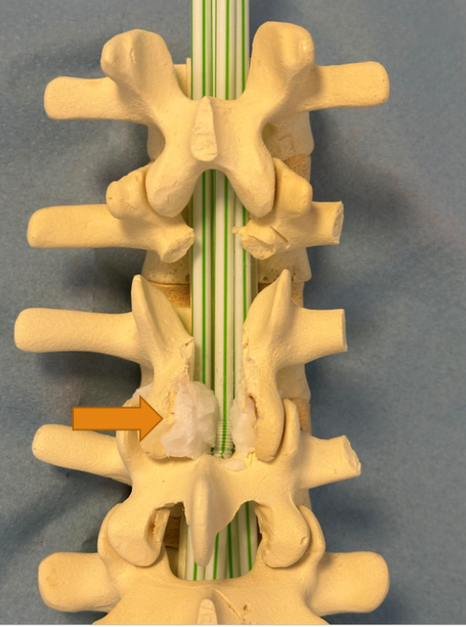

På modellen er vist, hvordan slidgigt i de små ægte led sammen med fortykkelse af ledbånd kan medføre forsnævring af rygmarvskanalen og dermed tryk på nerverne, som ligger i rygmarvskanalen. Pilene peger på væv, som typisk bliver forstørret ved slidgigt, og som derfor medfører forsnævringer. Det er forsnævringerne, som kan forklare, hvorfor der kommer nervesmerter i benene.

På det første billede ses, hvordan spinalnerven er klemt, inden den forlader rygsøjlen. På det andet billede ses, hvordan rygmarvskanalen forsnævres af fortykket væv ved slidgigt.